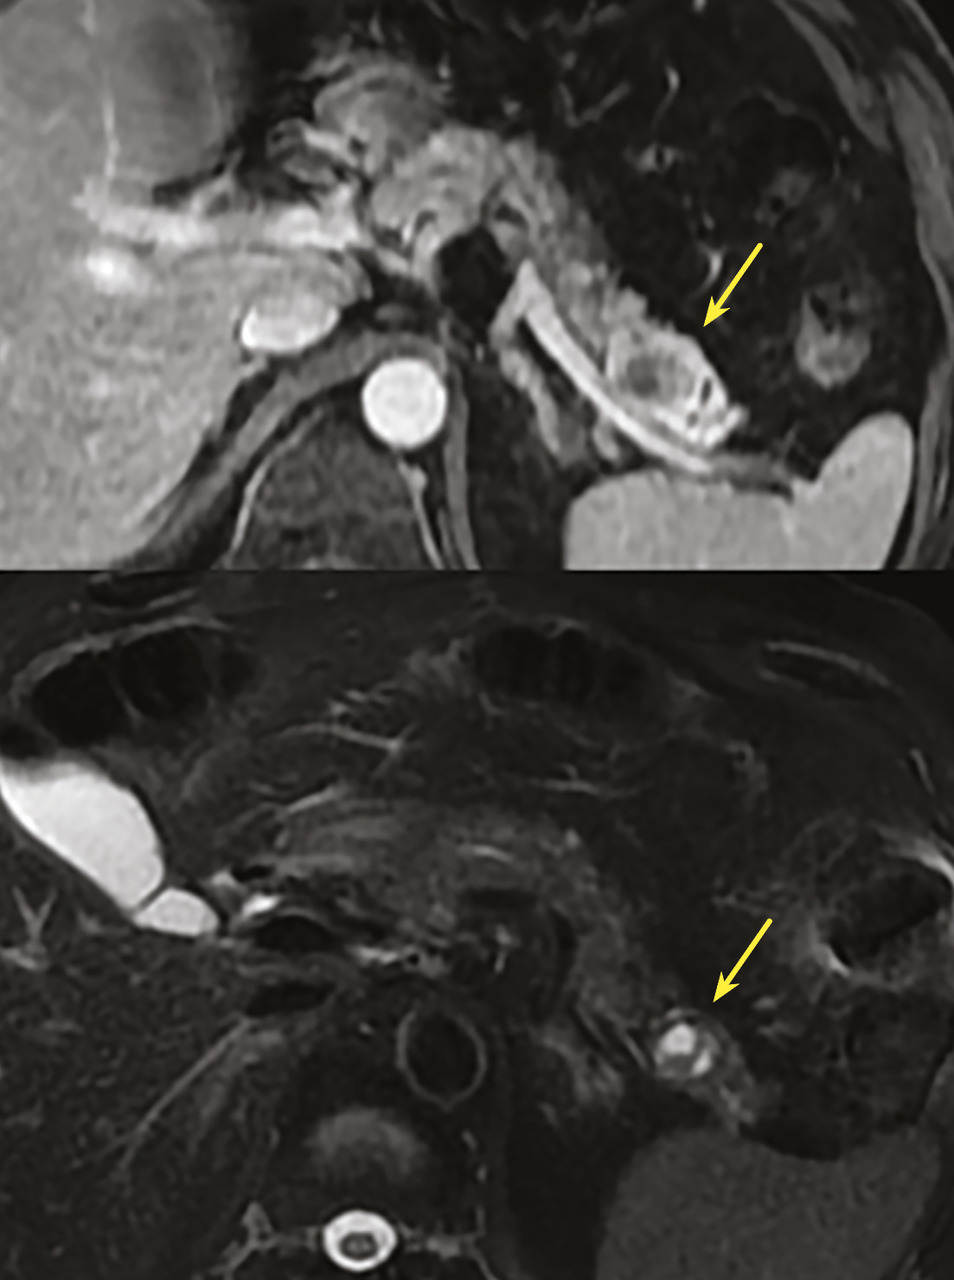

Rare et bénin, le kyste lympho-épithélial ne nécessite pas de surveillance particulière et aucune exérèse n’est recommandée. C’est une lésion de forme arrondie, uni- ou multiloculaire, polylobée, exopancréatique dans 75 % des cas, sans dilatation canalaire, avec un sex-ratio masculin (4 :1). La taille moyenne est de 30 à 40 mm. Il existe des amas de kératine visibles sous la forme de spots hyperéchogènes à l’échographie, hyperdenses en tomodensitométrie (TDM), hyper­intenses en T1 et hypo-intenses en T2 à l’IRM. Un contingent graisseux intralésionnel peut être mis en évidence à l’IRM.13

Rare lésion vasculaire bénigne d’origine lymphatique, congénitale (due à une anomalie de développement embryologique) ou acquise (liée à l’obstruction du tissu lymphatique par de la fibrose), le lymphangiome pancréatique ne nécessite pas de surveillance si le patient est asymptomatique car ce kyste est bénin sans risque de dégénérescence. Dans deux tiers des cas, il se situe dans la région corporéo-caudale et les espaces graisseux rétropéritonéaux. Sa taille peut varier de 2 à 20 cm. Si cette lésion se complique (hémorragie intrakystique essentiellement), une résection peut être réalisée et doit être complète pour limiter le risque de récidive locale.14

Toujours parmi les LKP rares à potentiel malin, on compte les tumeurs neuro-endocrines (TNE) kystiques (20 % des TNE pancréatiques) [fig. 5]. De découverte fortuite et non fonctionnelles, les TNE kystiques sont uniques, uniloculaires, bien différenciées, de bas grade, c’est-à-dire avec un indicateur de prolifération Ki67 < 3 %, et la présence d’une masse hypervasculaire (nodule) au niveau de la paroi. La partie charnue tissulaire peut être de petite taille.